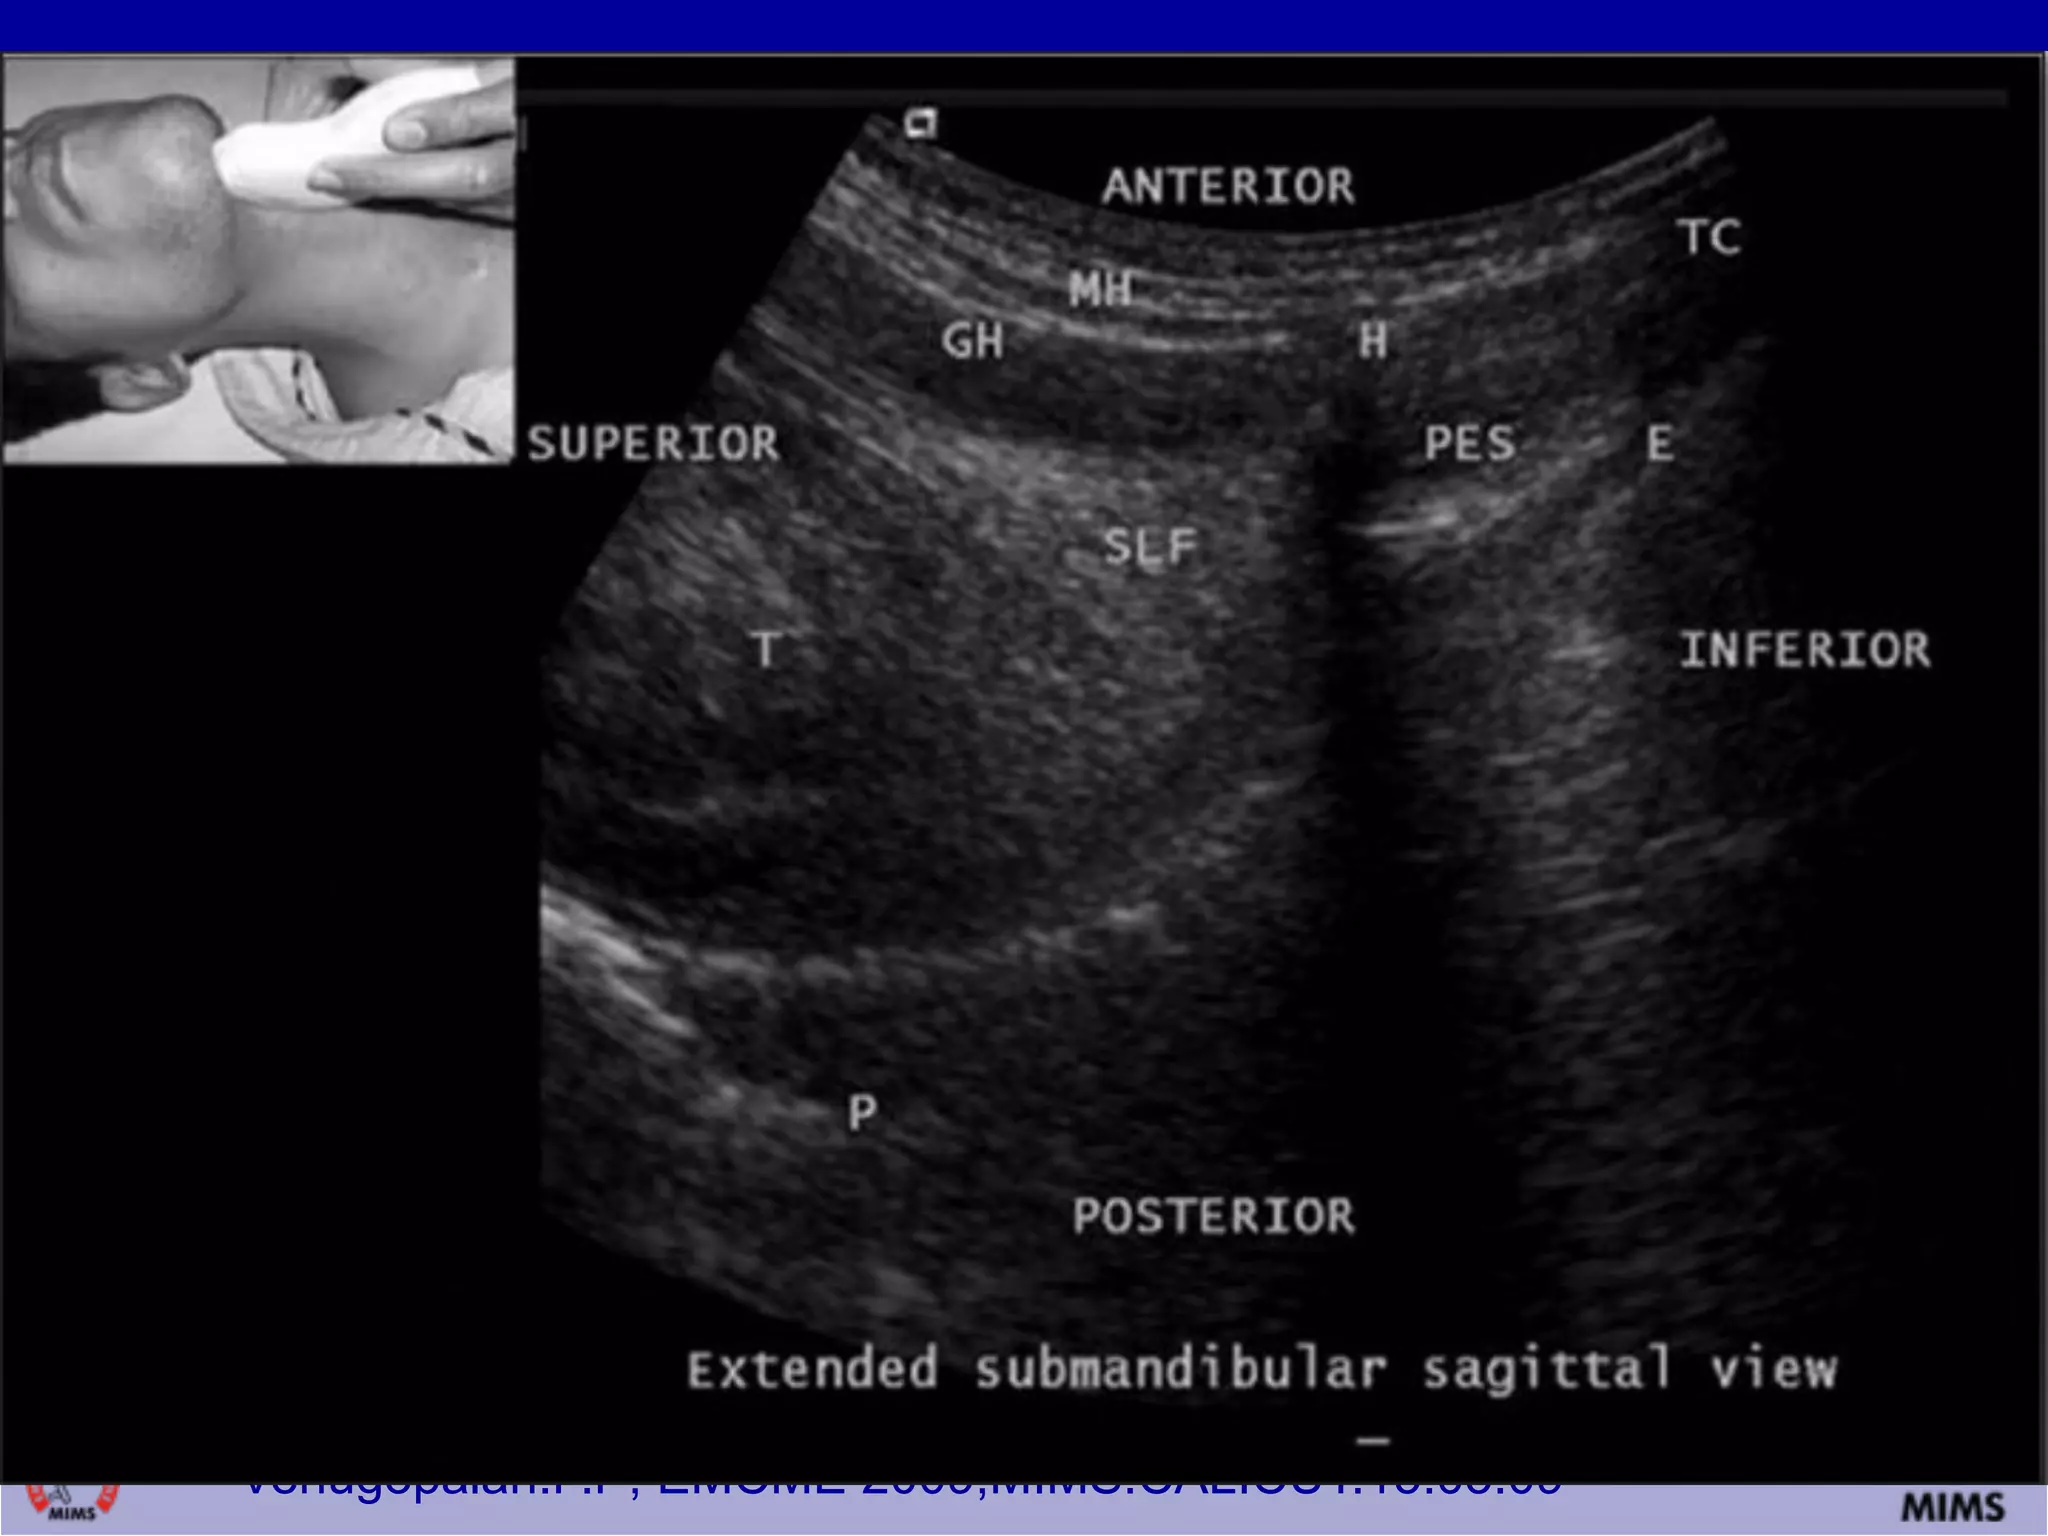

USG- EDD

» When ETCO2 detection is not possible,

» One novel approach Bedside ultrasound.